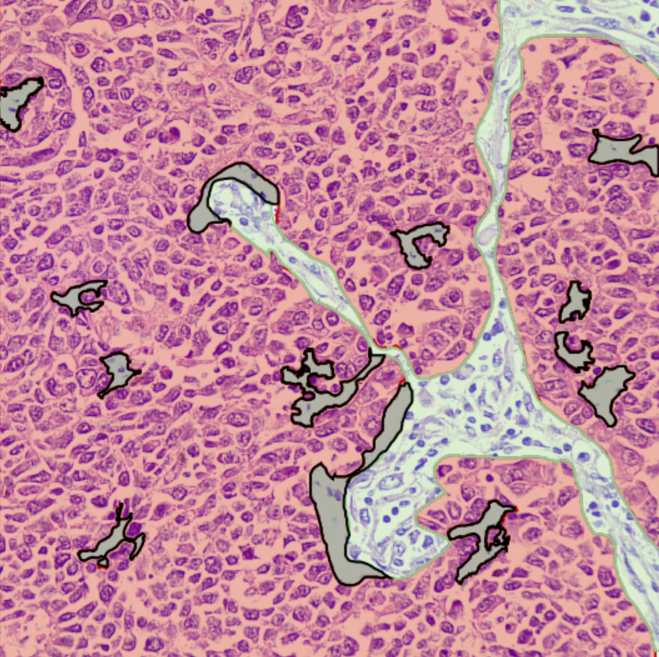

WSI & ROI Segmentation

Region-of-Interest marking, Tumor/Stroma segmentation, Lesion identification, and histological feature segmentation for model training.